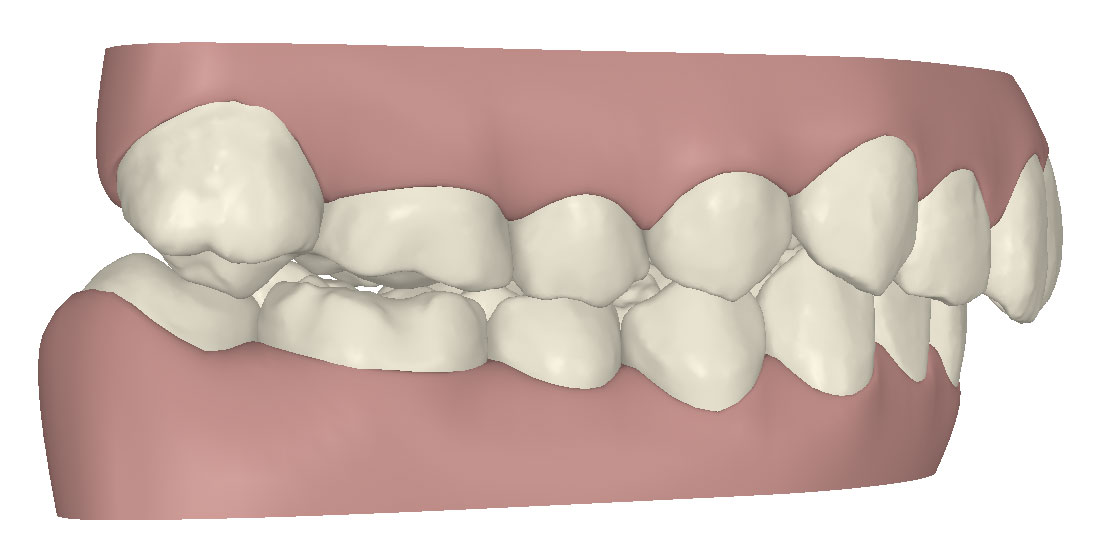

コンピューターを使って作製した透明なマウスピース型の矯正装置(アライナー)を段階的につけ替えていき、それにより歯列を矯正し、歯並びへと改善します。はじめに 治療開始から終了までのアライナーができあがってきます。マウスピース型矯正装置(インビザライン)の最大の特徴として「クリンチェック」というソフトがあります。3D のコンピュータ シュミレーション画像で、治療開始から完了までを目で見て確認することができます。

マウスピース型矯正装置(インビザライン)治療においては、クリンチェックというシミュレーションソフトを活用しております。

このクリンチェックの魅力は、治療前の現在の歯並びから治療後の歯並びを視覚化して患者様にご説明できる点にあります。

また、抜歯・非抜歯、全体矯正・部分矯正などそれぞれの治療パターンをシミュレーションすることが可能です。

| 治療前 |  |

| ライトプラン 隣接面削合なし |

| ライトプラン 隣接面削合あり |

| フルプラン 隣接面削合あり |